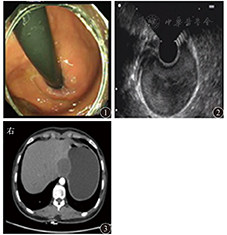

患者女,18岁,因上腹胀6个月于2013年9月23日入院。体检未见明显异常。胃镜检查示胃底近齿状线可见黏膜隆起,大小约3.0 cm×4.0 cm,表面光滑,颜色同周围黏膜(图1),胃镜通过贲门未感明显阻力。超声内镜示胃壁层次结构清晰完整,病变起源于黏膜下层,边界尚清,内部见均匀中等偏高回声,切面大小为3.4 cm×2.4 cm(图2)。胃二期增强CT检查示胃底近齿状线处胃腔外见结节状低密度影,直径大小约3.8 cm(图3),增强扫描边缘轻度强化。在内镜下标记病变后行黏膜下注射,剥离肿物表面黏膜,暴露黏膜下病变,病变触之尚软,表面见纤维膜包裹,切开后见咖啡色黏稠液体流出,充分引流及灌洗后切除部分囊壁送病理检查,并开放囊腔(图4),手术顺利,术后7 d出院。病理诊断为胃黏膜下囊性淋巴管瘤;HE染色见扩张的淋巴管成囊状,并见少许腺体成分及平滑肌组织增生;免疫组织化学检查结果为结蛋白、CD31、CD34、细胞角蛋白(cytokeratin,CK)20、Ki67、H.pylori阴性,特异性淋巴管内皮标志物D2-40(图5)、CK7阳性。术后5个月复查胃镜,未见复发(图6)。